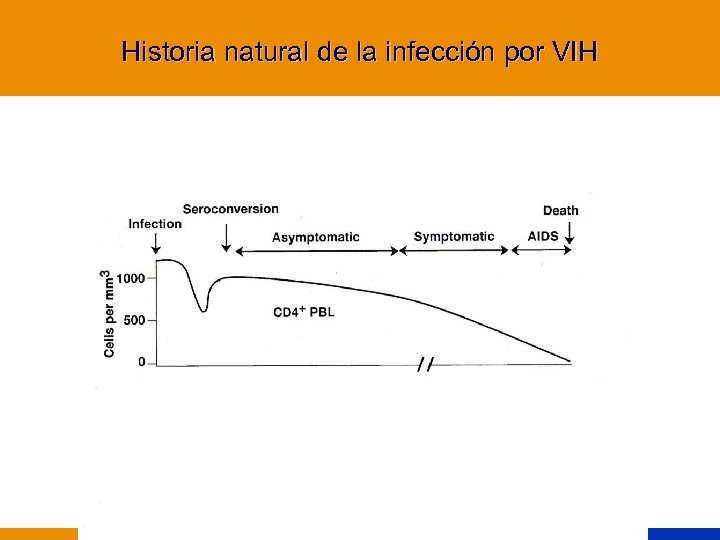

Historia natural de la infección por VIH

Historia natural de la infección por VIH

Meses Años después del inicio de la infección CMV MAC Herpes Toxoplasmosis Coccidioidomicosis Histopasmosis PCP TBC Muguet Leucoplasia vellosa Recuento de CD 4/mm 3 Historia natural de la infección por VIH

Meses Años después del inicio de la infección CMV MAC Herpes Toxoplasmosis Coccidioidomicosis Histopasmosis PCP TBC Muguet Leucoplasia vellosa Recuento de CD 4/mm 3 Historia natural de la infección por VIH